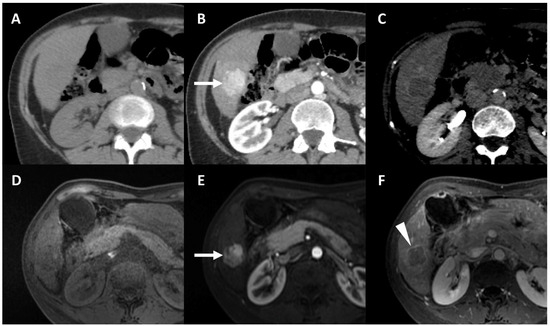

- Cannella, R.; Cunha, G.M.; Catania, R.; Chupetlovska, K.; Borhani, A.A.; Fowler, K.J.; Furlan, A. Magnetic Resonance Imaging of Nonhepatocellular Malignancies in Chronic Liver Disease. Magn. Reson. Imaging Clin. N. Am. 2021, 29, 404–418. [Google Scholar] [CrossRef] [PubMed]

- Shin, J.; Lee, S.; Hwang, J.A.; Lee, J.E.; Chung, Y.E.; Choi, J.-Y.; Park, M.-S. MRI-diagnosis of category LR-M observations in the Liver Imaging Reporting and Data System v2018: A systematic review and meta-analysis. Eur. Radiol. 2022, 32, 3319–3326. [Google Scholar] [CrossRef]